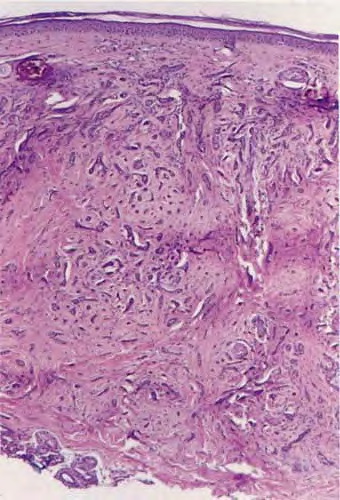

microcystic-adnexal-carcinoma